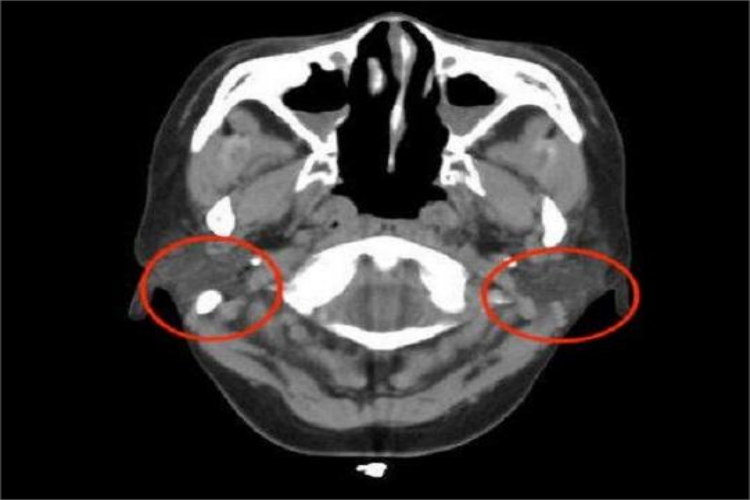

腮腺:CT图像上,腮腺位于下颌骨后,胸锁乳突肌前,上至颅底,位于乳突尖和颞颌关节之间,下至下颌角。腮腺是脂肪性腺体组织,密度低于周围的肌肉密度,但高于皮下、颞下窝及咽旁间隙内的脂肪。在腮腺实质内的血管能清楚显示,在增强图像显示更清楚。腮腺导管造影后CT扫描,能清楚勾画出导管的解剖结构,显示其粗细、走行及其变异。

颌面部CT对于颌面部组织病变的发现、诊断及其范围确定等,均有重要价值。比如通过CT下腮腺腺体形态、大小和密度的变化,可以判断病变的部位及蔓延范围,良性肿瘤与恶性肿瘤的鉴别,以及腮腺外肿瘤的侵犯。

若有良性肿瘤,其CT特征是肿块多呈类圆形,边缘光整,密度均匀,其中血管瘤有明显强化。恶性肿瘤的形态多不规则,边界模糊,密度不均匀,肿块内常有出血、坏死或囊变,常侵犯周围软组织及脂肪间隙,颅底骨质破坏及淋巴结转移。